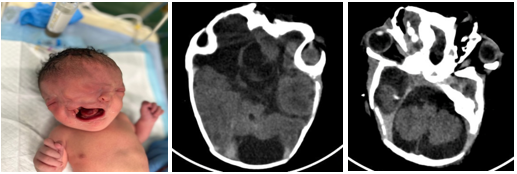

A brain CT scan (Figure 1) showed multiple facial malformations with facial multiplicity. Normal morphology of the anatomical structures in the posterior fossa multiple bilateral supra-tentorial hemispheric malformations presence of a mega cisterna magna and posterior fossa. Partial agenesis of the right cerebral hemisphere, particularly the right frontal lobe, and to a lesser degree on the left side. Agenesis of the corpus callosum asymmetry in the expansion of the lateral ventricles, primarily on the right side large arachnoid cyst in the anatomical location of the right frontal lobe.

Figure 1 Brain CT scan.